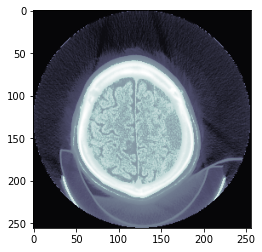

plt.imshow(data_scaled, cmap=plt.cm.bone);

data_scaled = dcm.hist_scaled(min_px=100, max_px=1000)